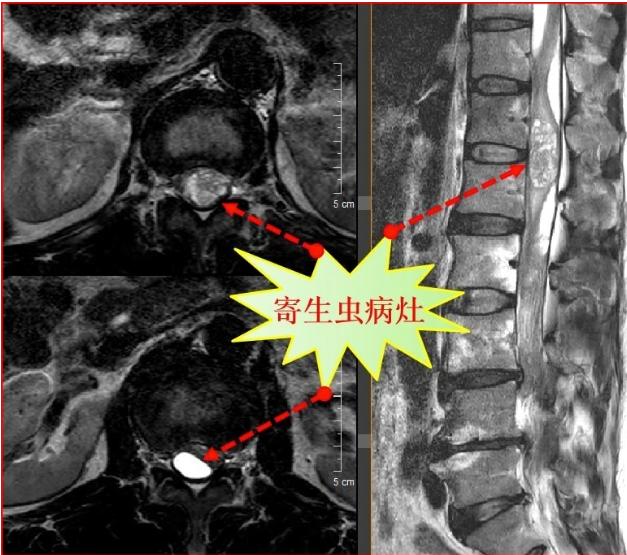

描述:近日,一位男子在醫院接受治療,引起了廣泛關注。據悉,該男子長期以來有著一個不尋常的嗜好,每天堅持吞食蛇膽并飲用蛇藥,結果竟然導致他15年后突發重病。這一離奇的案例引發了醫學界的深思和警醒,大家紛紛呼吁我們要更加珍惜生命,正確看待養生方式。

然而,好景不常,命運似乎對他開了一個惡作劇的玩笑。近日,他突發劇烈腹痛,隨即被緊急送往醫院。經過詳細的檢查和專家的診斷,醫生們愕然地發現,他的膽囊中充滿了結石,嚴重影響了正常排泄功能。

有關專家表示,長期吞食蛇膽和飲用蛇藥,雖然在一定程度上可以起到提高免疫力的作用,但是其中所含有的毒素和化學物質,同樣會對人體的內臟器官產生不可逆轉的傷害。尤其是膽囊作為排毒器官,接受過多的毒素刺激后會產生結石等并發癥,嚴重危害人體健康。